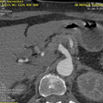

Aorta CR

从内部显示主动脉走形,显示其整体状况和其分支的起源